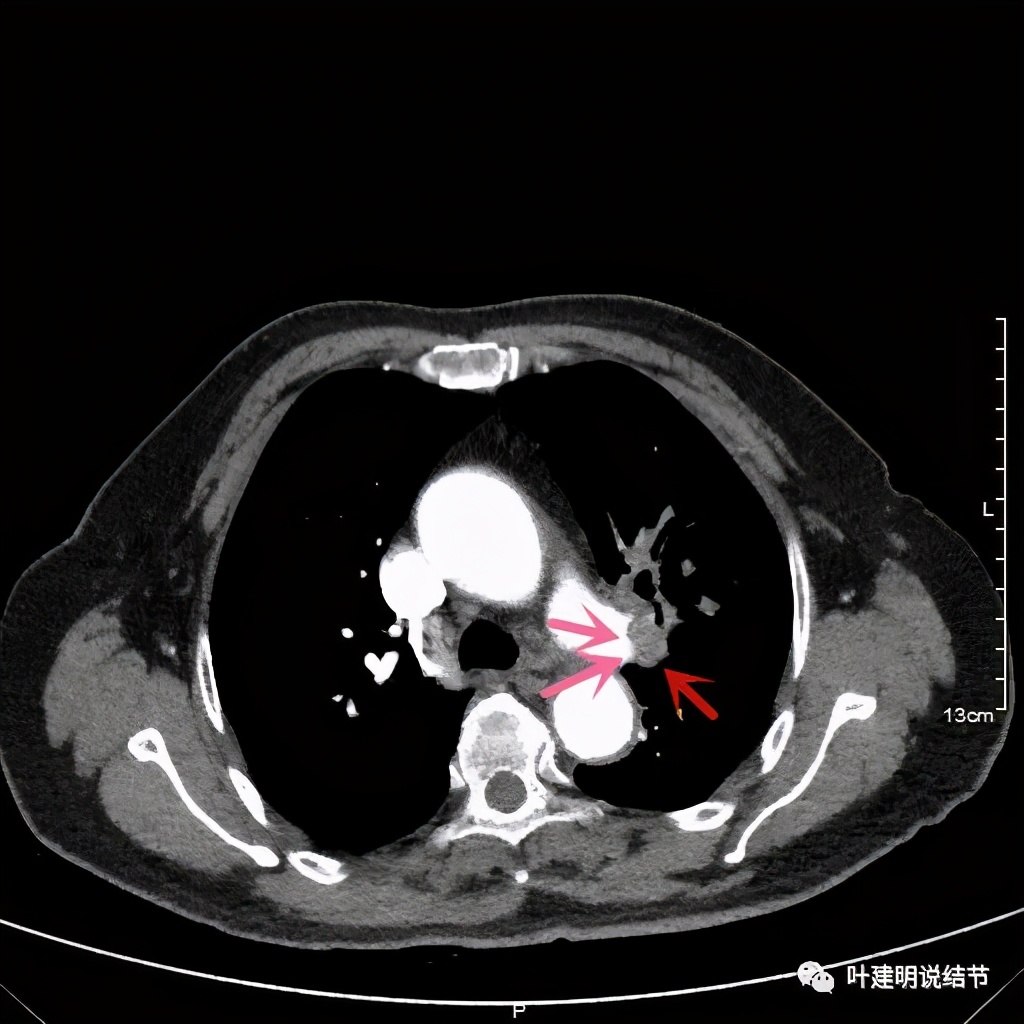

上图示肺动脉与肿瘤的关系仍紧密

上两图示叶间肺动脉的上缘与肿瘤没有界限

延长切口后解剖游离,发现上肺静脉能被游离解剖出来,但肿瘤把上叶支气管后壁、左肺动脉第一支、叶间肺动脉及其向上叶的分支均紧密愈着在一起,根本分不出缝隙。我们采用先断开下叶支气管与左主支气管,然后直视下切开上叶支气管前壁,一点一点往后壁切,尽量避免伤及肺动脉,等后壁完全脱开后,肺动脉无法分开部分,将叶间动脉的部分血管壁以及其往上叶的分支均用切割缝合器离断并半合残面,这样虽然叶间肺动脉有所变细,但仍有5-7毫米以上直径,预计下叶功能并不会有太大影响。取走标本后,再行左主支气管与下叶支气管的吻合。吻合前送切缘: